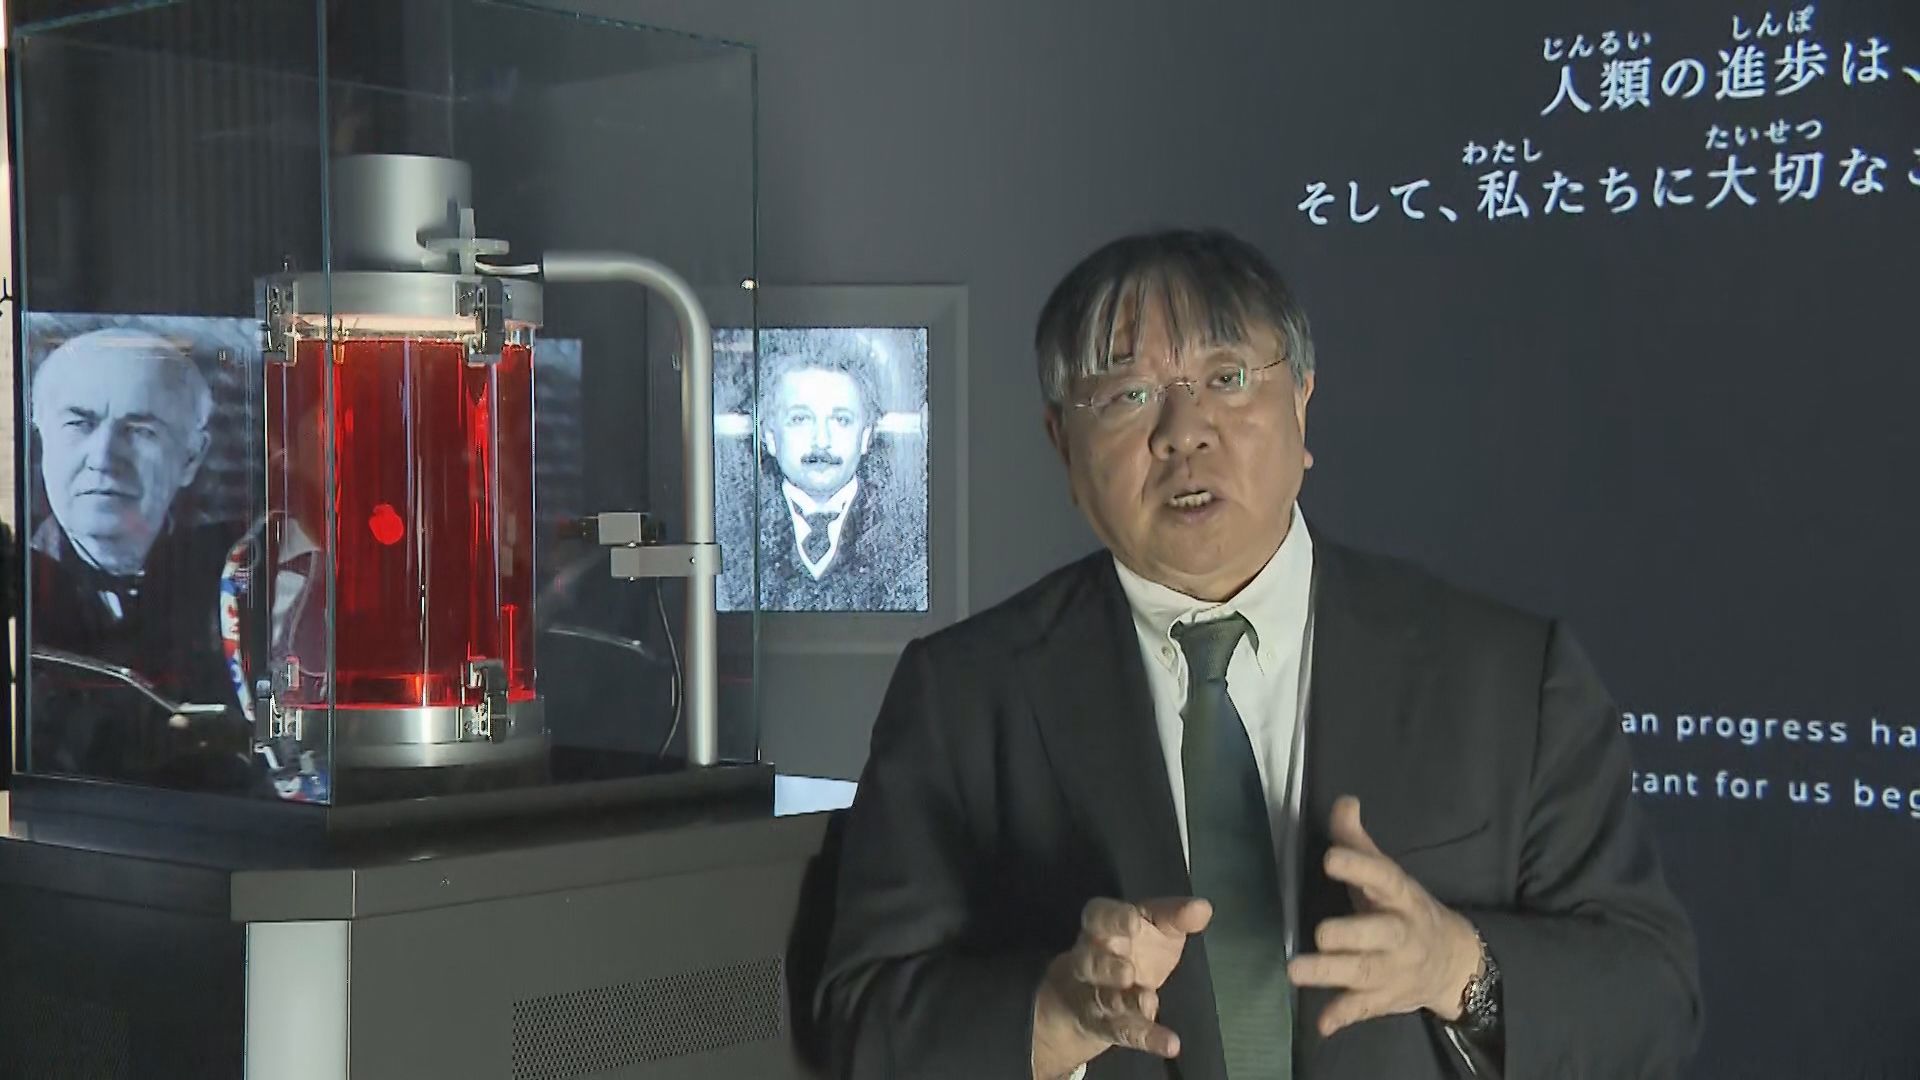

■万博の目玉「iPS心臓」に挑んだ医師と科学者

大阪・関西万博の目玉の一つ「iPS心臓」モデル。

iPS心臓モデルを手がけるのは、大阪大学発のベンチャー企業「クオリプス」。

最高技術責任者を務めるのが大阪大学の澤芳樹特任教授(70)だ。

この心筋シートの技術を応用し、作成されたのが万博の「iPS心臓モデル」だ。

奥田さんの「心臓を吊り下げる」という発想には、研究を見守っていた澤教授も驚いたという。

【大阪大学・澤芳樹特任教授】「もう突然、開幕の1年ぐらい前に、奥田君が僕に『心臓が動き出しました』って言ってくれたんです。それまでは、ほとんど動いてなかったんですよ。こんなこと技術的にできるわけがないと思っていたら、奥田君が『できた』っていうから、『ほんまか?』って言って。それで、奥田君が『ぶら下げた方がいいです』と」

「糸で吊ることで、動き出すということがわかったので、これも『サイエンス』ですよね。吊らなかったら動かないのに、吊ったら必ず動くんだというところで再現性がある」

「なぜ吊ったら動くかということが大事で、おそらく心筋細胞に与える重力とか、いろんな影響があるのかもしれない。もともと持っている遺伝子じゃなくて、環境因子がそういう影響を与えて、細胞の性格を変えたがために、寝ていたら動かなかったのが、立てたら動くようになるというね」